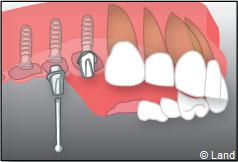

Exemple de 3 dents manquantes remplacées par 3 couronnes sur implants.

Pose des piliers prothétiques et des 3 couronnes scellées.